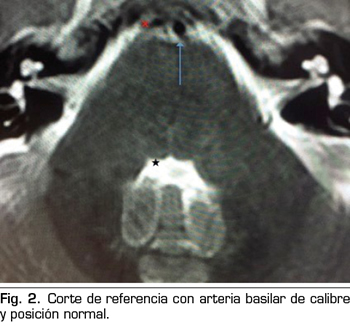

Presentamos el caso de un varón de 59 años, que cursa con un cuadro de parálisis del VI par craneal derecho, tras una cefalea postpunción dural, secundaria a una punción dural accidental durante una epidural. En la resonancia magnética, aparece un compromiso del espacio de la arteria basilar sobre la emergencia del VI par derecho. Posiblemente, esta variante anatómica vascular, lo haya predispuesto a una mayor vulnerabilidad del nervio abducens. La tracción del nervio, pudo producir una isquemia, convirtiendo a la hipotensión licuoral en el posible desencadenante de la parálisis. Con tratamiento conservador se recuperó completamente.

Figura 2